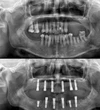

التهاب حول الزرعة السنية (بيري إمبلانتتس)

فقدان الأسنان

التهاب الغشاء المخاطي حول الزرعة السنية (بيري-إمبلانت ميكوزيتس)